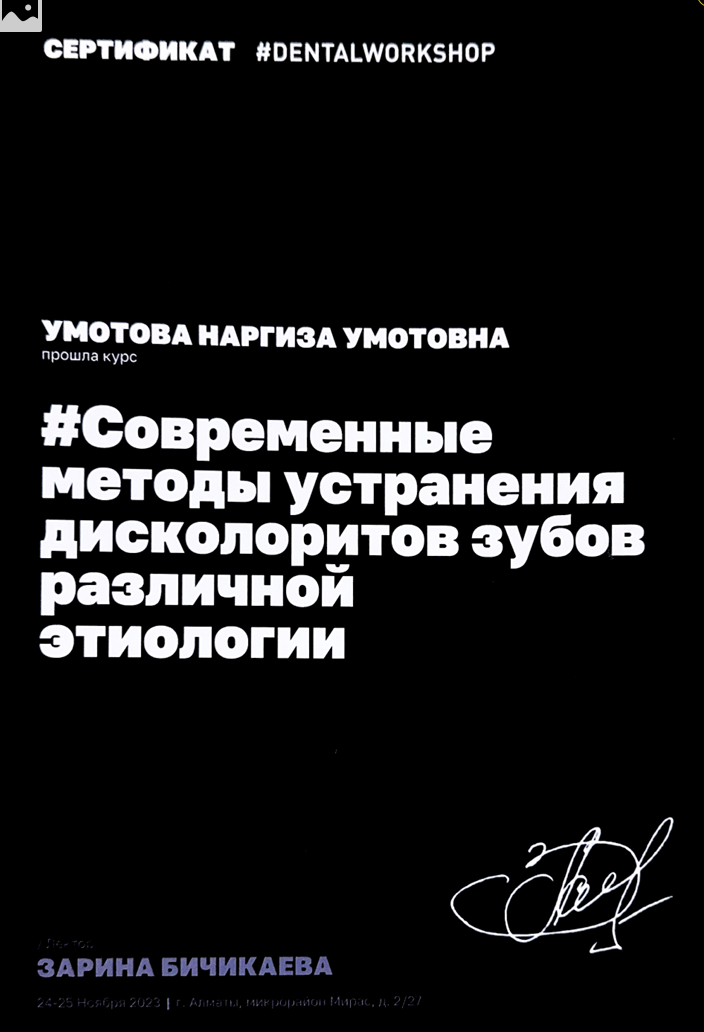

Умотова Наргиз Умотовна

Более 8 лет помогает пациентам сохранять здоровье зубов и красивую улыбку